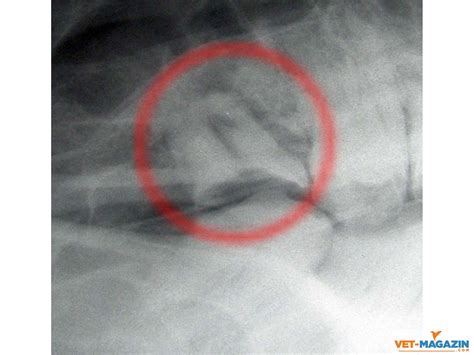

• Imaging Tests: In some cases, imaging tests like X-rays or CT scans may be ordered to visualize the sinuses and check for blockages or infections.

• Nasal Endoscopy: A thin, flexible tube with a camera is inserted into the nasal passages to get a closer look at the sinuses and nasal structures.